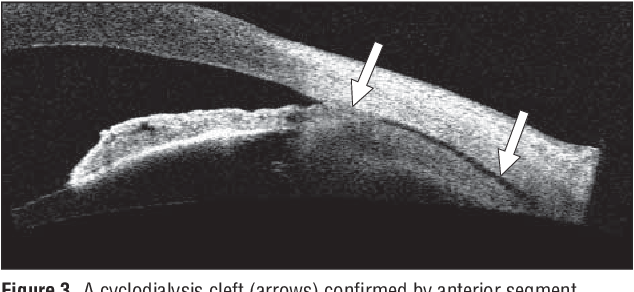

섬모체해리 틈새 (cyclodialysis cleft)

섬모체해리 틈새란 섬모체가 섬모체가 붙어있어야하는 공막부위로부터 떨어지는 것을 말합니다.

이는 홍채절제술을 할 때 과도하게 당기게 되면서 홍채와 붙어 있는 섬모체가 당겨지면서

공막부위로부터 떨어지는 경우가 가장 흔합니다.

섬모체는 안구내에서 방수생성을 담당하는 위치인데, 섬모체 해리가 발생하게되면,

해당부위의 섬모체는 기능을 잃어 저안압이 빠지거나,

섬모체로부터 방수의 흐름이 비정상적으로 흘러들어가, 섬모체와 공막사이 공간 혹은 맥락막과 공막사이의 공간(suprachoroidal space)에 고이게 되면서 이차적인 문제를 발생시킵니다.